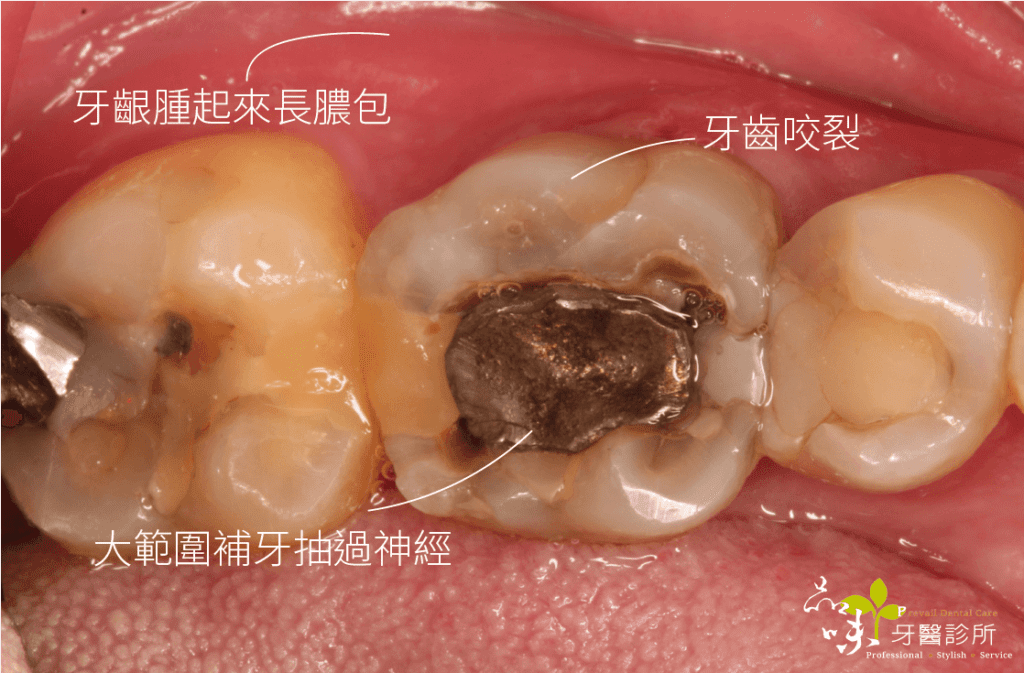

下午診間走進一位牙齒劇烈疼痛的陳先生(化名)。左手捧著下巴,疼痛難耐地說:「醫師,今天不小心咬到骨頭,現在只要一喝水就感到抽痛,痛到無法咬東西,請問這顆牙怎麼辦?」

經過臨床檢查後,我發現這顆牙已呈現牙根斷裂的狀況,依目前醫療常規只能把斷裂的牙齒拔除。

「這顆牙拔掉後,我想要做植牙,但是聽朋友說植牙會很痛,而且要等很久的時間⋯⋯」陳先生焦慮地問著。